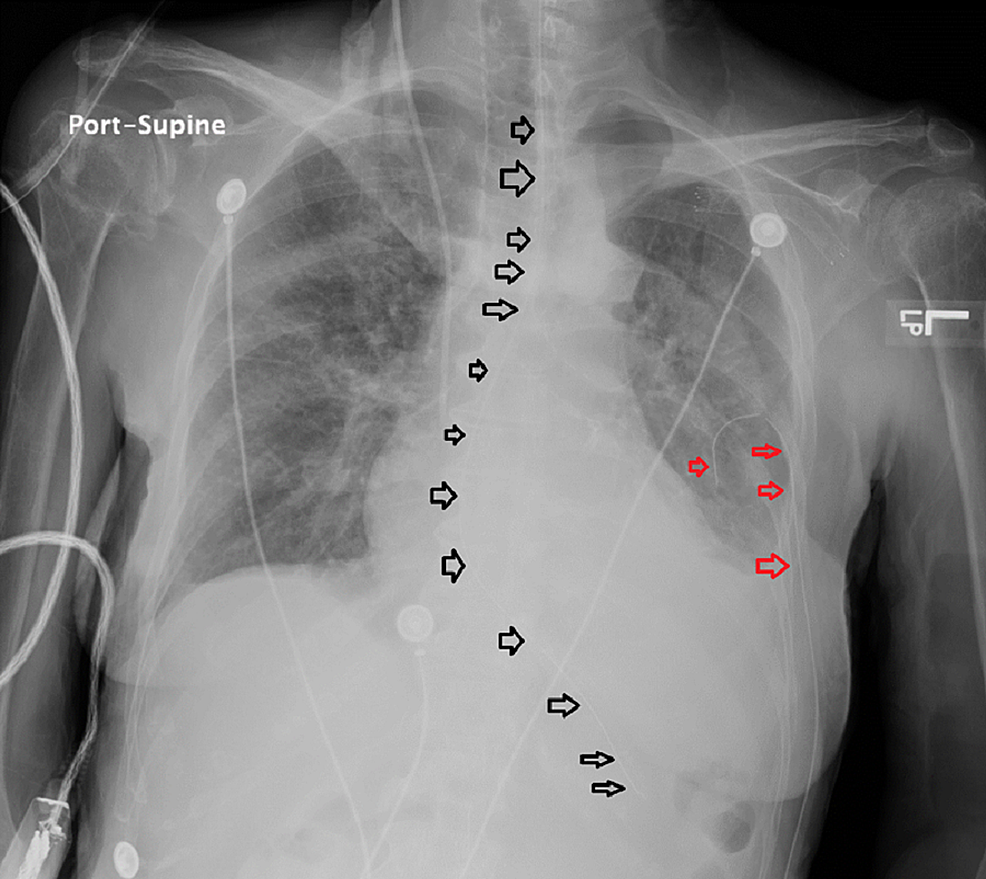

Chest xray after chest tube removal with apical pneumothorax and... Download Scientific Diagram

Chest xray after chest tube removal with apical pneumothorax and... Download Scientific Diagram How To Remove Chest X Ray Spot It is very reassuring if your nodule is the same size as it was on past imaging. Another possible cause of a lung nodule is a granuloma, a benign rounded scar resulting from many. a bacterial infection. This surgical procedure involves removing the. A ct scan is an. a doctor may request a thoracotomy to remove a cancerous. How To Remove Chest X Ray Spot.